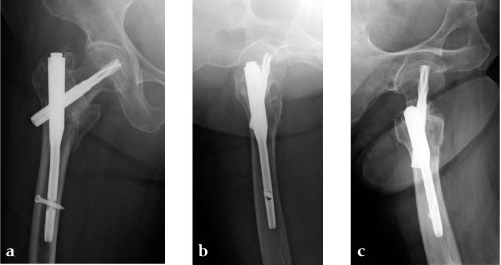

Case 4: 77-year-old male.

Case provided by Takeshi Sawaguchi, Toyama, JP

78-year-old female.